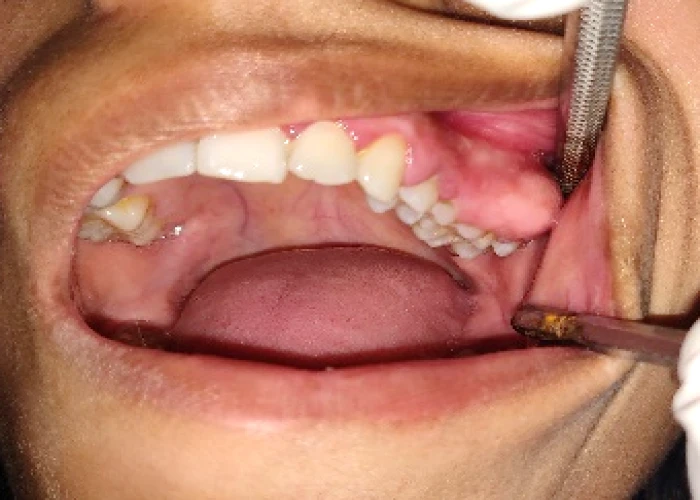

Oral Medicine & Radiology is concerned with diagnosis and medical management of diseases specific to the oral & maxillofacial structures, management of oral manifestations of systemic diseases, management of behavioral disorders, and dental treatment of medically compromised patients. It deals with the diagnostic intraoral and extraoral imaging of maxillofacial structures by both conventional and digital methods. It further includes Forensic Odontology and also promotes tobacco cessation.

Oral Medicine & Radiology is the Gateway to Dentistry. It provides high quality clinical diagnostic training for management of potentially malignant disorders and oral cancer, medical emergencies, training in tobacco cessation, chair side investigative procedures, Basic Life Support, and LASER, apart from general dentistry. It also provides exposure in forensic odontology, specialized training in diagnostic digital imaging.